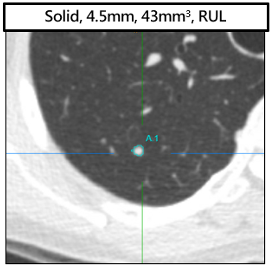

自動產生肺結節相關資訊,進行肺結節的辨識(identification)、分割(segmentation)與分類(classification),提供:

- 肺結節種類(Solid, Part-solid, Non-solid)

- 所在肺葉位置 (LUL, LLL, RUL, RML, RLL)

- 最大徑、平均徑、體積

- 影像位置(Slice, Series number(SE), Instance number(IM), Slice location(SL), Slice thickness(ST))